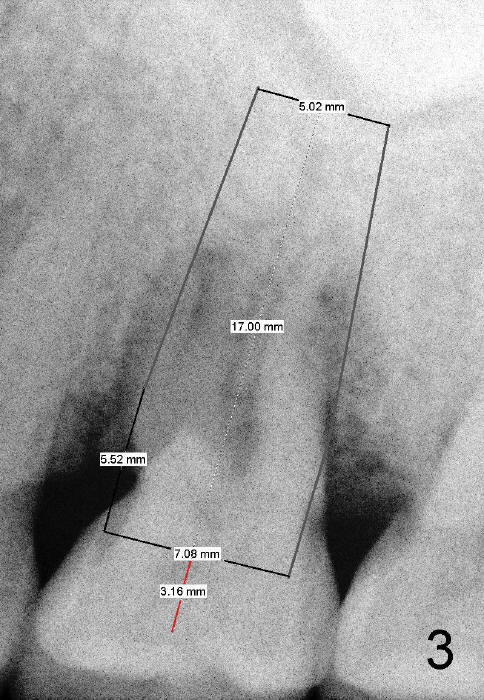

Bone density around the molars (including apical to #14) (Fig.1 black *) is higher than that around the premolar (white *). In fact the tooth has horizontal root fracture (Fig.2: <: CEJ), consistent with high bone density (strong mastication). An immediate implant is planned (Fig.3). After extraction, osteotomy starts at the buccal slope of the palatal (Fig.4 P) socket. Because of high bone density apical to the sockets, drills are required for osteotomy in the septum (type II bone) instead of osteotomes and primary stability is easily achievable (>60 Ncm). When a 7 mm implant (Fig.6 I)) is placed, the peri-implant gaps are much smaller (*) than that with a 4.5 mm tap (Fig.5 T). This helps bone grow faster toward implant. A long implant (17 mm) is necessary for this case to obtain primary stability in the apical one (double arrows in Fig.6). With reamers, a fair amount of autogenous bone is harvested during drilling, mixed with allograft and synthetic bone and placed in the remaining buccal (Fig.7) and palatal (Fig.8) sockets. The openings of the buccal and palatal sockets are covered with collagen dressing (C) and perio dressing. The latter is kept in place by a short abutment (Fig.6-8 A).